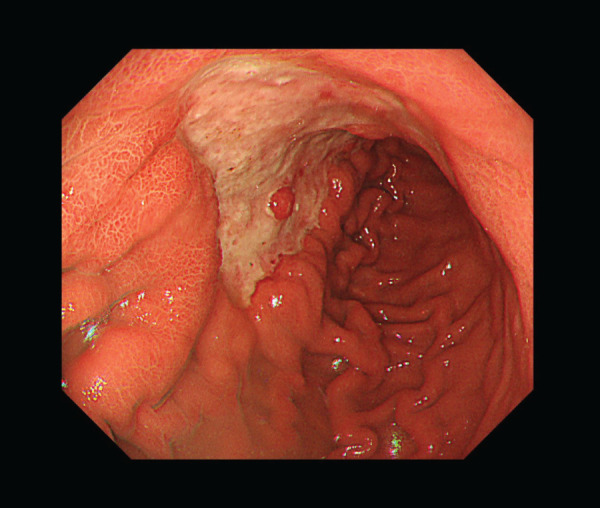

Case presentation: A 65-year-old woman presented with chronic epigastric pain and was diagnosed with gastric cancer through upper gastrointestinal endoscopy. The endoscopy revealed an ulcerated mass at the lesser curvature of the middle gastric body, and a biopsy confirmed a moderately differentiated adenocarcinoma. A laparoscopic distal gastrectomy was initially planned. However, the surgical approach was converted to an open total gastrectomy because of the spread of the tumor to the greater curvature of the gastric body and enlargement of the distal lymph nodes of the splenic artery, which were not included in the planned lymphadenectomy. Postoperatively, the patient experienced no abdominal pain or fever. However, on POD 7, blood tests revealed elevated hepatobiliary enzymes, and a contrast-enhanced CT (CECT) scan showed a loss of flow in the splenic artery and vein, leading to a diagnosis of extensive splenic infarction. A follow-up CECT scan 3 months later revealed a notable reduction of the splenic parenchyma over time.